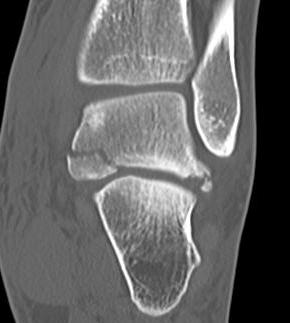

Osteochondral lesion